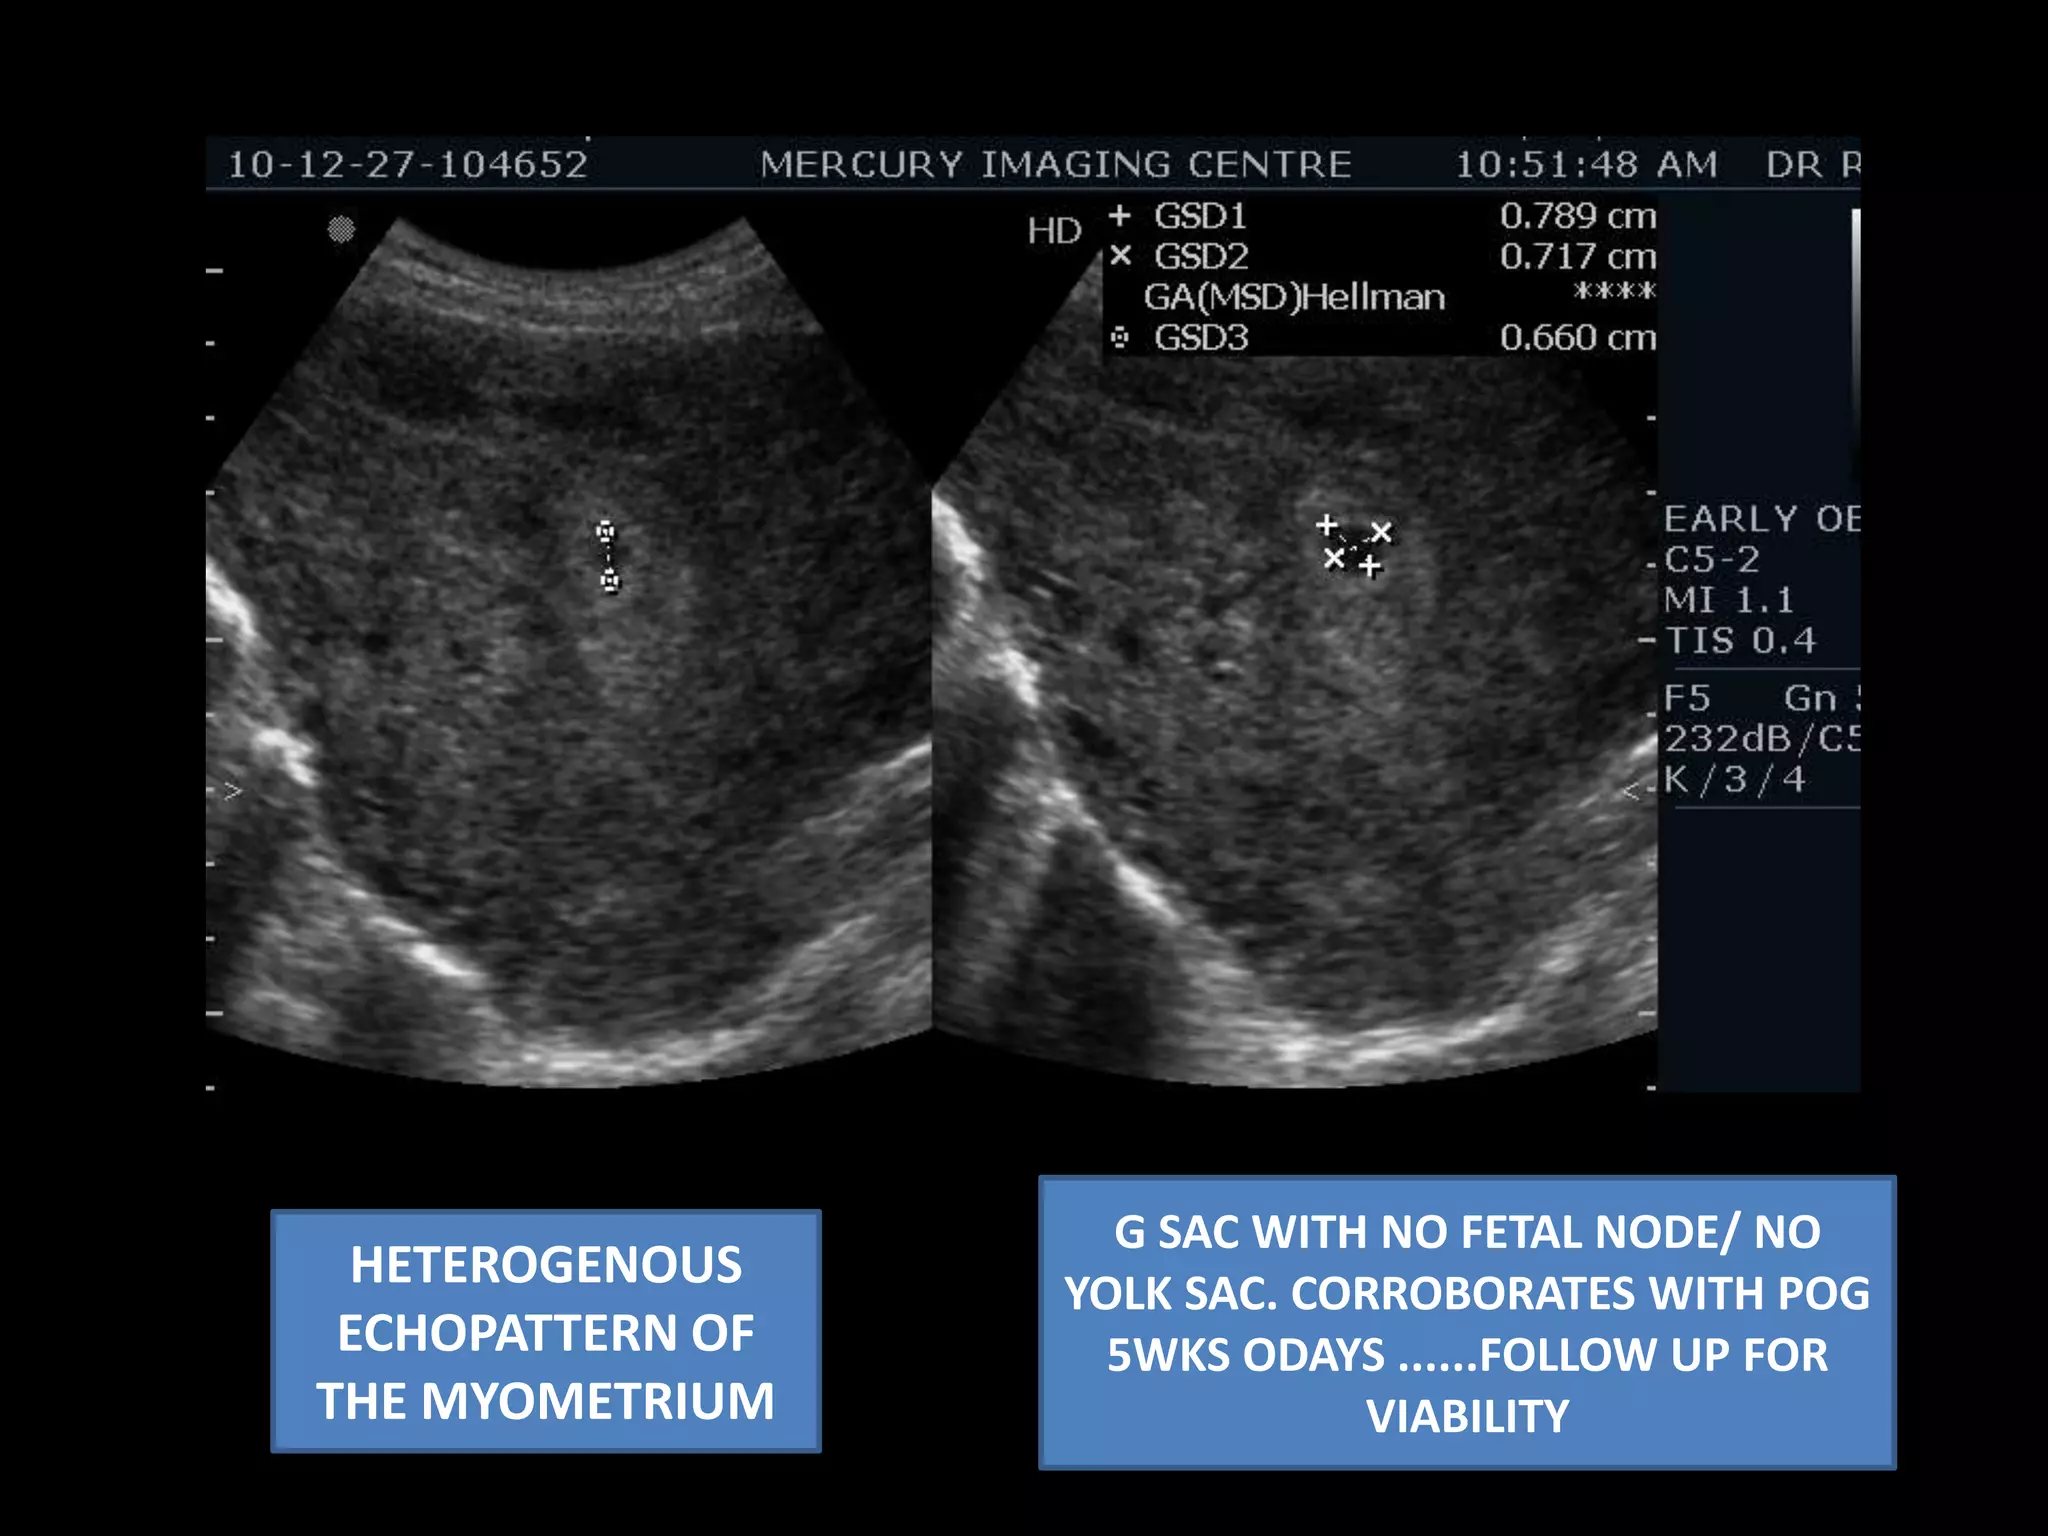

G SAC WITH NO FETAL NODE/ NO YOLK SAC. CORROBORATES WITH POG 5WKS ODAYS ......FOLLOW UP FOR VIABILITY  HETEROGENOUS  ECHOPATTERN OF THE MYOMETRIUM

G SAC WITHNO FETAL NODE/ NO YOLK SAC. CORROBORATES WITH POG 5WKS ODAYS ......FOLLOW UP FOR VIABILITY HETEROGENOUS ECHOPATTERN OF THE MYOMETRIUM